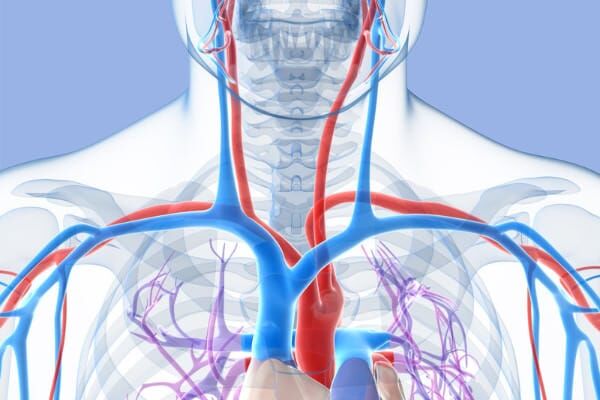

Arterial TOS is the least common form of TOS, but it is a very serious disease. Bony structures compress the subclavian artery in the thoracic outlet and cause local arterial damage. Cervical ribs are more likely to cause arterial TOS than any other form of TOS.

Arterial TOS occurs when anatomic structures in the thoracic outlet compress the subclavian artery and create local or distal symptoms. Specifically, arterial compression causes local arterial damage, including arterial narrowing or aneurysm. In addition, blood clots can form in the damaged arterial segment, and cause distal arterial occlusion.